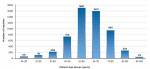

Implants were placed in patients aged 13 years old to 95 years old. The distribution of implants by patient’s age is shown in Figure 17. Patients 21 to 30 years of age had the highest rate of success at 95.8%.